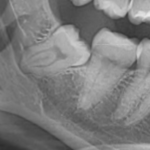

Edentulie, mobilità dei denti, ascessi, protesi mobili sia parziali che totali, bocca urente, disfagie, problemi socioeconomici, difficoltà nel muoversi per fare la spesa, il prevalente acquisto di cibi pronti all’uso e preconfezionati, problematiche psicologiche collegate alla diminuzione del numero di amici o alla perdita del coniuge con conseguente isolamento, la monotonia alimentare spesso causata ed associata a difficoltà nella masticazione ed a malattie croniche, un ridotto senso della sete, ebbene sono questi i fattori che portano i nostri anziani a deficit nutrizionali, con carenze subcliniche di vitamine e minerali e con un conseguente rischio di malnutrizione.

Va però sottolineato che lo screening nutrizionale, con le misure antropometriche (peso, BMI – indice di massa corporea – circonferenza corporea, pliche cutanee, composizione corporea), deve essere necessariamente associato ad un esame parodontale eseguito rilevando tutti i parametri biometrici necessari (presenza degli elementi dentari, profondità di tasca, mobilità dentaria, quantità di gengiva aderente presente) sì da assicurare una corretta ed adeguata masticazione dei cibi, così importante per la digeribilità ed assimilabilità degli stessi.

Questo perché un programma nutrizionale, anche se magistralmente preparato, funziona solo e soltanto se i nostri denti e le nostre gengive sono presenti ed in salute, rendendo quindi efficaci e concreti questi nostri proponimenti alimentari.

Insomma, se non hai i denti, se hai protesi mobili, se hai dolore, se hai fastidio in bocca, bruciori, sanguinamento, qualsiasi piano nutrizionale è destinato ad un fallimento, più o meno marcato, che può portare ad una patologia chiamata malnutrizione.

Perdita dei denti

Ed ecco quindi l’importanza del mantenimento di una completa dentizione la cui perdita, oltre ad una importante difficoltà della masticazione sia come quantità di cibo sia come qualità, porta inevitabilmente ad una perdita di interesse agli alimenti, ad una ridotta socializzazione al momento del pasto e, conseguentemente, ad una diminuzione dell’introito alimentare.

Integrità del cavo orale

L’integrità del cavo orale è quindi basilare per una corretta e completa alimentazione e per combattere efficacemente la malnutrizione senza dover ricorrere alla prescrizione di alimenti specifici, specie nei nostri anziani.